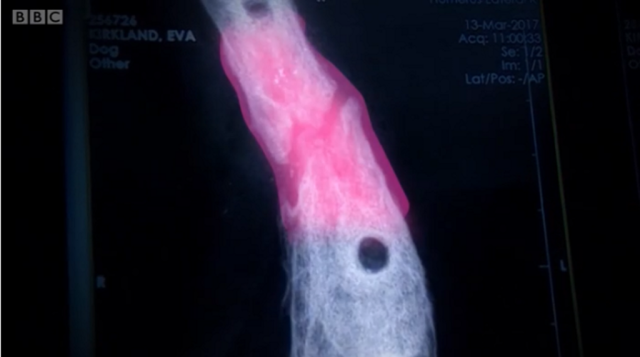

Собака не міг ходити, того як його збила машина і він отримав перелом ноги. Травма була настільки серйозна, що довелося відрізати кінцівку. Проте її врятували науковці, у лабораторії вони виростили з частини кістки – нову.Науковці вкрили частину кістки пластмасою та хімічними речовинами – через 6 тижнів кістка була повністю зцілена. Це перше таке лікування в світі, передає ВВС Україна.